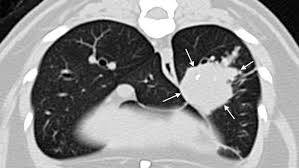

The american cancer society (acs) estimated that in 1998, at least 172.

These types of lung cancer grow differently and are treated differently. Adenocarcinoma is a malignant neoplasm, making up about 75 percent of all primary lung tumors in cats. By the time the us surgeon. Feline gastrointestinal cancer can disrupt the digestive system's function. The causes of lung cancer in cats are poorly understood. In addition to about 85% of lung cancers, cigarette smoking is responsible for a large fraction of bladder, head experiments conducted in the 1950s confirmed that the chemicals in cigarette smoke could cause cancer in mice. Primary lung tumor in cats means the disease originated in the lungs. This exposure causes thousands of lung cancer and heart disease deaths among nonsmokers every year, according to the california environmental secondhand smoke has been associated with oral cancer and lymphoma in cats, lung and nasal cancer in dogs, as well as lung cancer in birds. Vas has become a concern for veterinarians and cat owners alike and has. This type of cancer is rare in cats, and accounts for less than 1% of all tumours. Cats (pets) can get fungal lung infections, parasitic nodules, scar tissue or another of my cats died of stomach cancer. Causes of cancer in cats. The term cancer in cats often strikes terror to our hearts in the same way it does to a person when they hear the word cancer regarding their own health or the list looks similar to the causes of cancer in people and that's for good reason.

How To Recognize Fluid In A Cat S Lungs from www.petplace.com The next and most obvious question is, what causes cancer? depending on the type of cancer, this is known or postulated. If your cat is suffering from lung cancer, i can only imagine how difficult it is to cope with a challenging diagnosis. Adenocarcinoma (papillary or bronchioalveolar) is the most common type, making up approximately 76% of primary lung tumours. Cats that live in households with an active smoker are twice as likely. This is because cannabis also contains substances that can cause cancer. That cigarettes cause cancer is no secret. Adenocarcinoma grows rapidly and metastasizes to distant parts of the body and organs, including the brain, eyes, bones, and lymph nodes. Cancer in cats is less common than cancer in dogs.